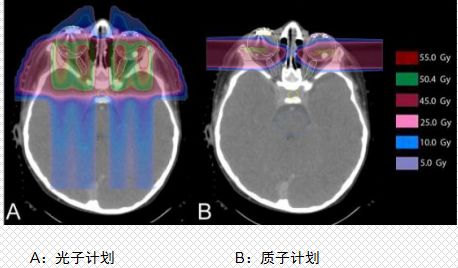

对于眼癌的患者,质子治疗可以在避免眼球摘除手术的前提下达到相同的治疗效果。眼部肿瘤的质子治疗计划,很清楚地看到质子治疗病灶周边非常干净,没有多余的射线残留,而传统放疗波及范围就很大了,对于眼睛这一重要器官,治疗时尤其要注意并且要尽最大努力进行保护,质子治疗有绝对的优势。而放疗相关的或原位出现的第二恶性肿瘤的10年发病率有显著差异(质子vs光子:0%vs14%)